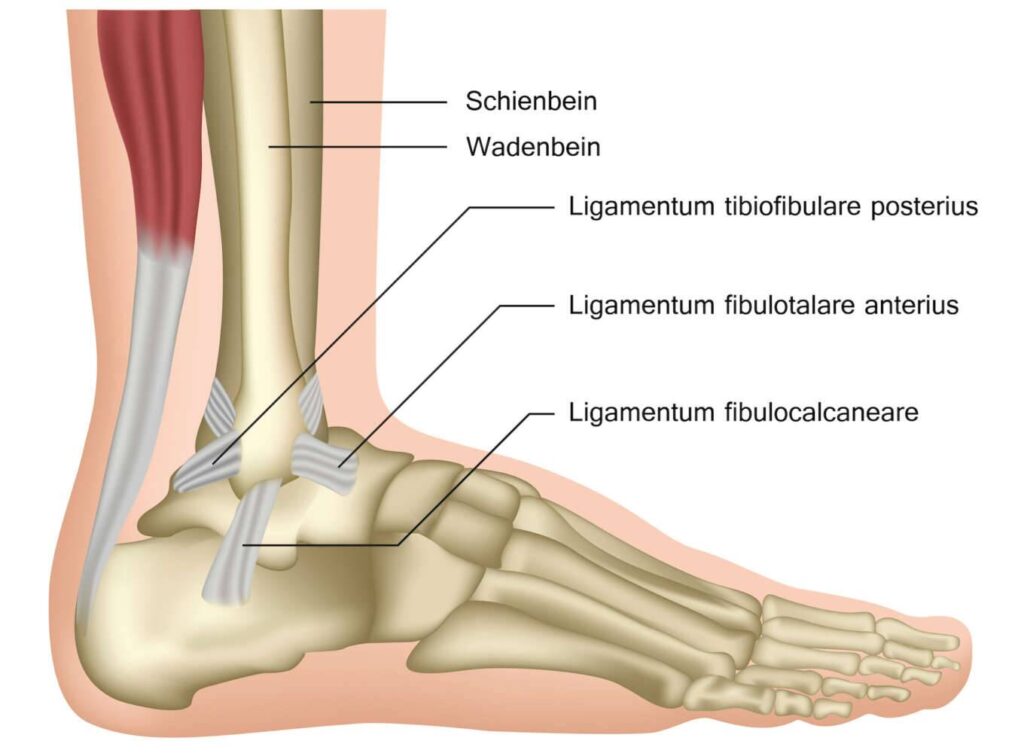

Wie sieht die Fuß Anatomie des Sprunggelenks aus?

Das Sprunggelenk ist eine komplexe Struktur, die aus verschiedenen Knochen, Gelenken, Bändern, Sehnen und Muskeln besteht.

| Knochen | Schienbein, Wadenbein, Sprungbein |

| Gelenke | oberes und unteres Sprunggelenk |

| Bänder | mediales und laterales Band, Syndesmose |

| Sehne | Achillessehne, Peronealsehne |

| Muskeln | Wadenmuskulatur |